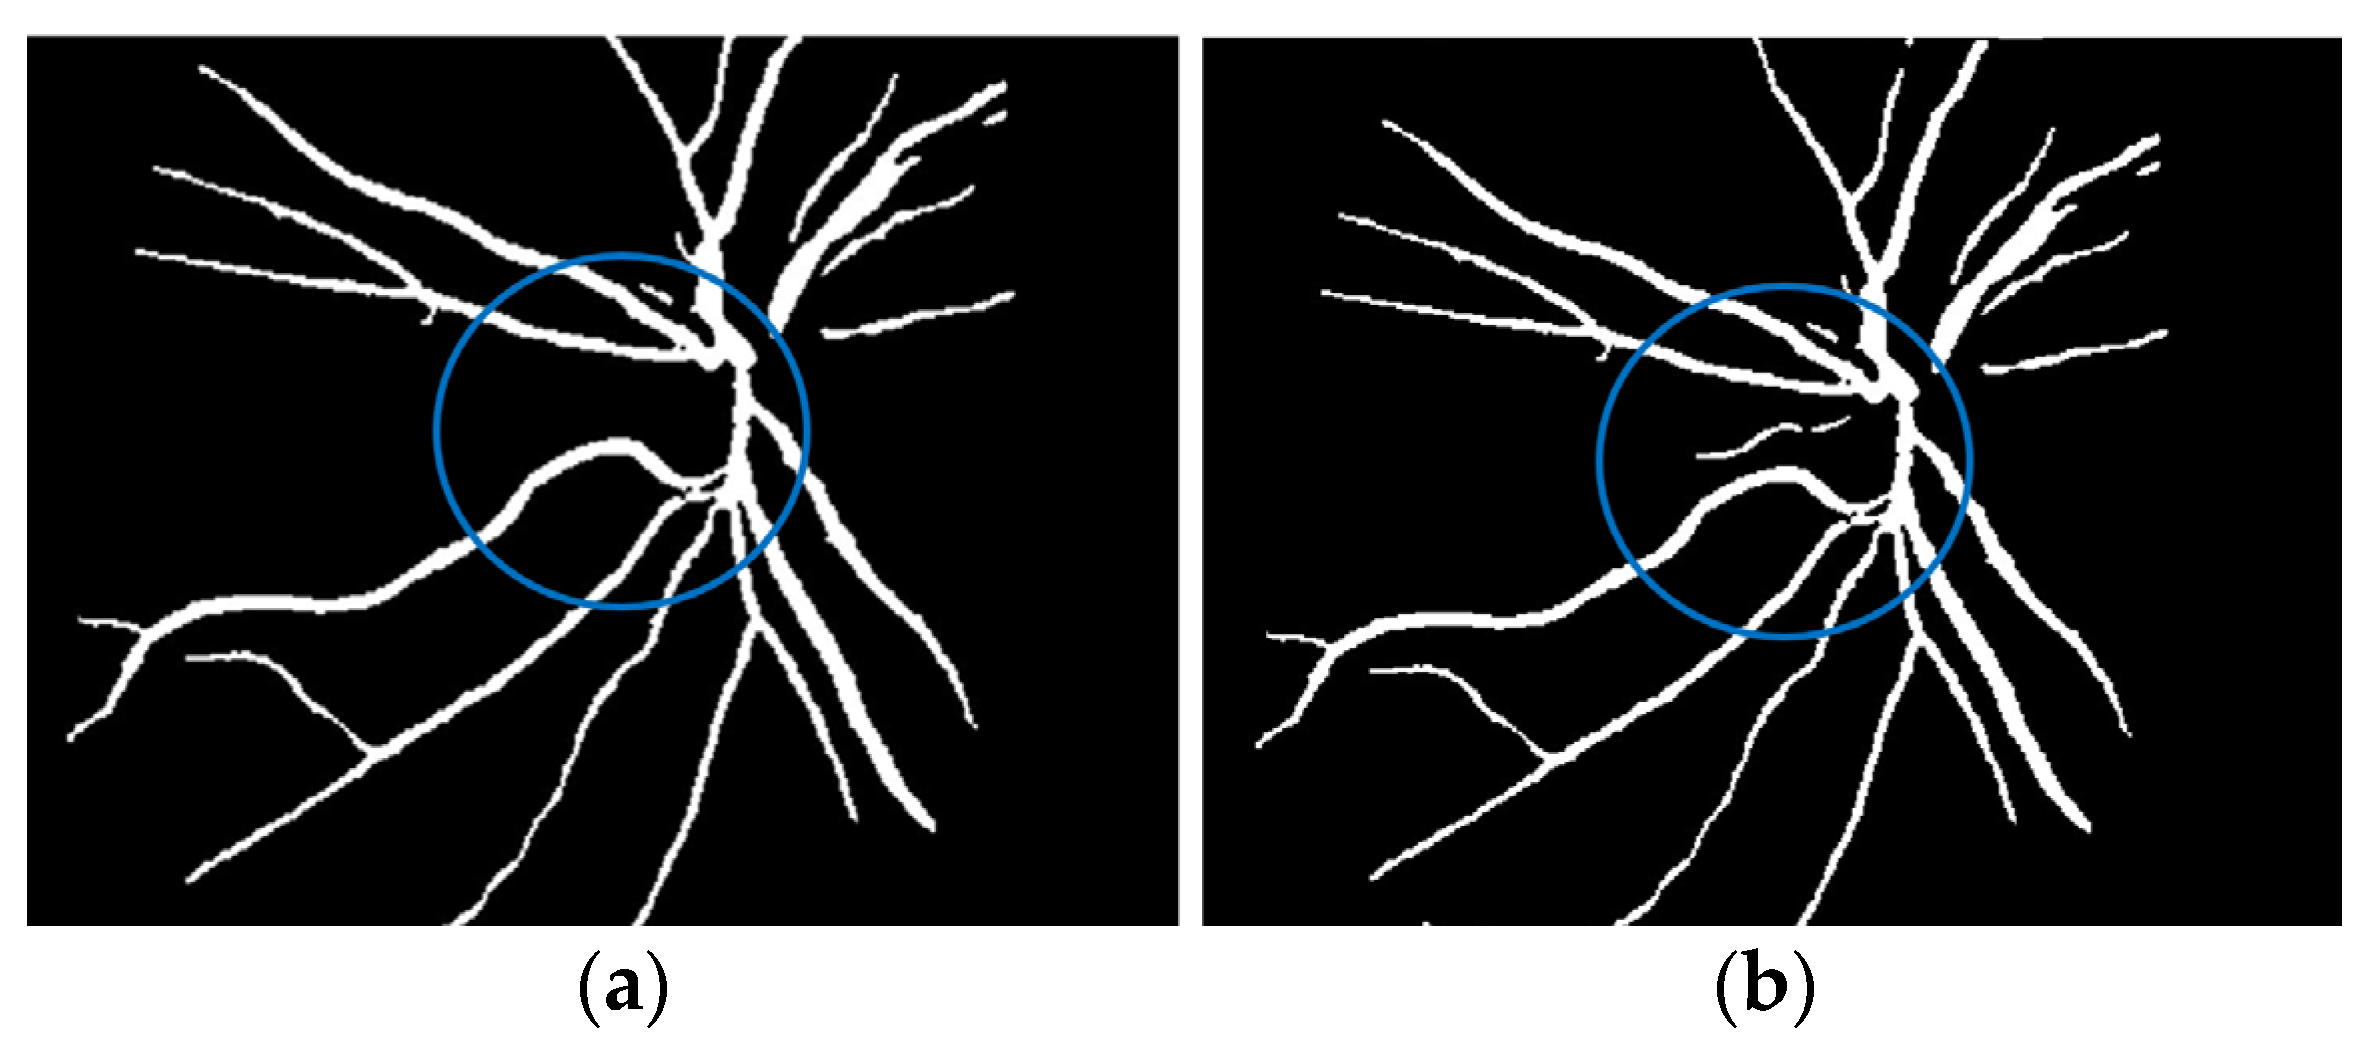

where f(vessel, background) corresponds to the input image, g(vessel, background) denotes the binary pixel after thresholding, and 128 is the optimal value to classify the histograms between the two classes. Any pixel (vessel, background) in the image at which f(vessel, background) ≥ 128 is extracted as a vessel pixel; otherwise, the pixel is regarded as a background point or a non-vessel pixel. The extraction result is displayed in Figure 8, where pixels with intensity values greater than 128 (retinal blood-vessel pixels) are shown in white against a background of black. As shown on the left side of Figure 8a, there are a few false extractions; they segment the actual retinal blood vessels (white pixel) as the background (black pixel). The Dilatation-Based Function is added to optimal thresholding functions to reduce the false negative value (see Figure 8b).

Figure 8.

Comparison of the extraction results with WKFCM false extraction and adding morphological dilation operator: (a) intensity thresholding with a loose extraction using WKFCM, (b) intensity thresholding using the proposed Dilatation-Based Function technique (demonstrated within the blue line).

where the extracted image’s pixel value is |SM| and the ground-truth image’s pixel value is |GT|, while |GT∩SM| represents the common elements between the ground-truth and the extracted images, and |GT + SM| represents the total number of pixels in the image. The addition of the proposed improvement of the WKFCM method to the extraction, based on the morphological dilation functions and optimal global thresholding, is displayed at the right of Figure 9. I confirmed that false extraction values were reduced and proposed a more accurate image of vessel extraction.

Figure 9.

Cross-dataset extraction result comparison of the retinal images from three datasets: (a) DRIVE dataset (first row), (b) STARE dataset (second row), (c) DiaretDB0 dataset (third row).